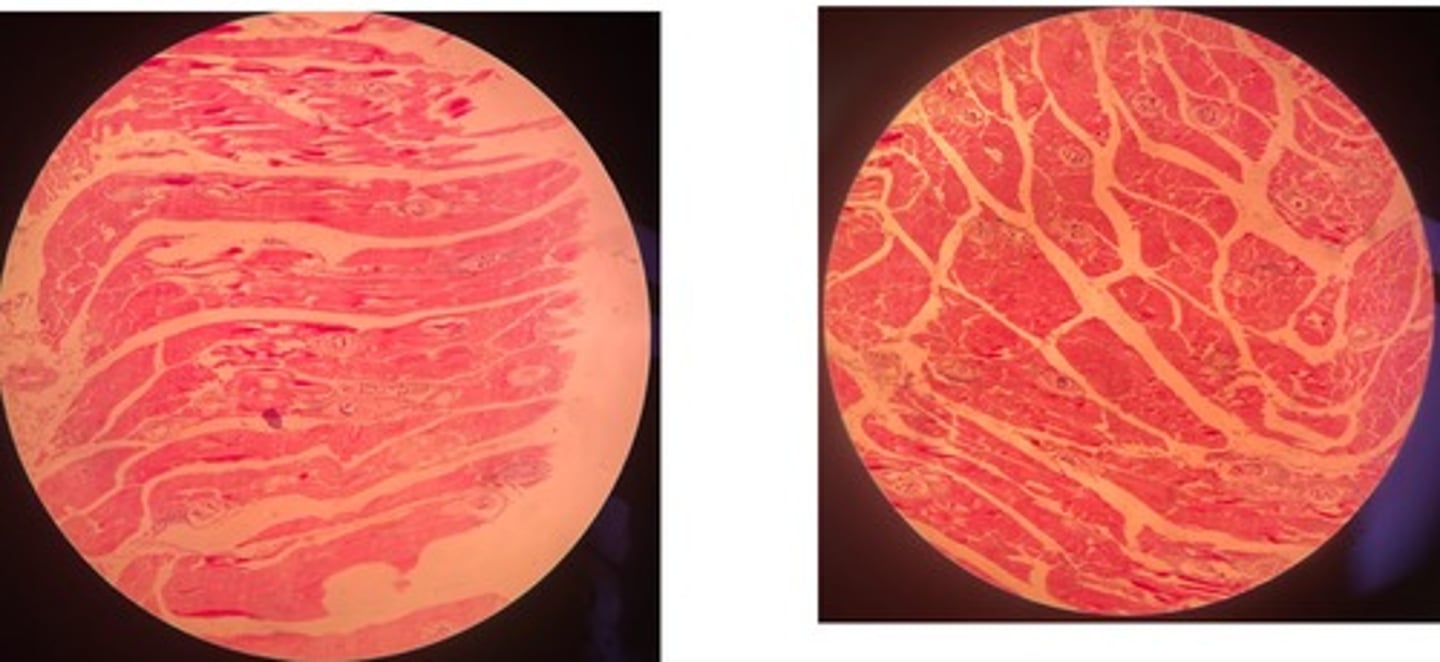

Trichinellosis

- Early: parasite within myocytes +infiltrate cells

- Late: normal morph w/ thick capsule and possible accumulation of Ca salt

Lymphoma

- many lymphoblasts infiltrating muscle fibres => atrophy + degen

- mitotic figures